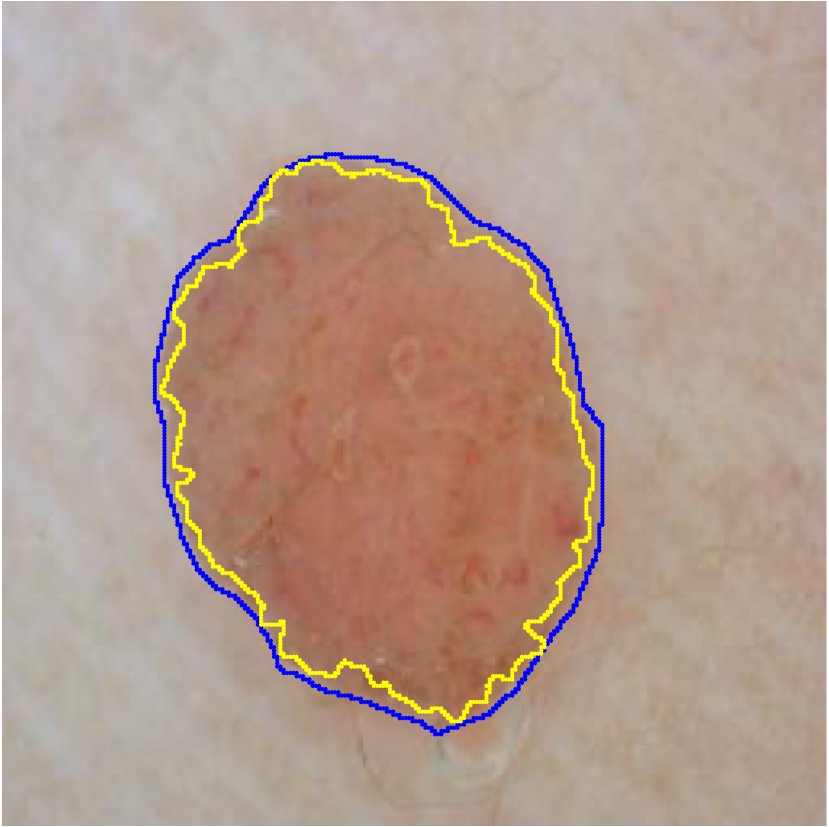

For each of these three datasets, we use three noise settings, denoted by , and . and are two settings synthesized by our Markov process with (expansion) and (shrinkage), respectively. Figure 4 shows examples of our synthesized label noise. We also include the mix of random dilation and erosion noise used by previous work (Zhu et al., 2019; Zhang et al., 2020b; a). This is achieved by randomly dilate or erode a mask with a number of pixels. Note that our Markov label noise can theoretically include this type of noise by setting . Detailed parameters for these settings are provided in the Appendix.

Table 1 shows the segmentation results of different methods with synthetic noisy label settings on JSRT , ISIC 2017 and Brats 2020 dataset. Note that QAM cannot be applied to Brats 2020 dataset because their network is designed for 2D only. We compare DICE score (DSC) on testing sets (against the clean labels). For each setting, we train 5 different models, and report the mean DSC and standard deviation. In and , where biases show up in noisy labels, the proposed method outperforms the baselines by a big leap in total case. The compared methods, however, only work when little bias is included, like . is equivalent to setting in our Markov model, resulting in . We also test the proposed method on real-world label noise, results shows in Table 2. Figure 5 shows examples of label correction results. We provide more qualitative results in the Appendix A.4.